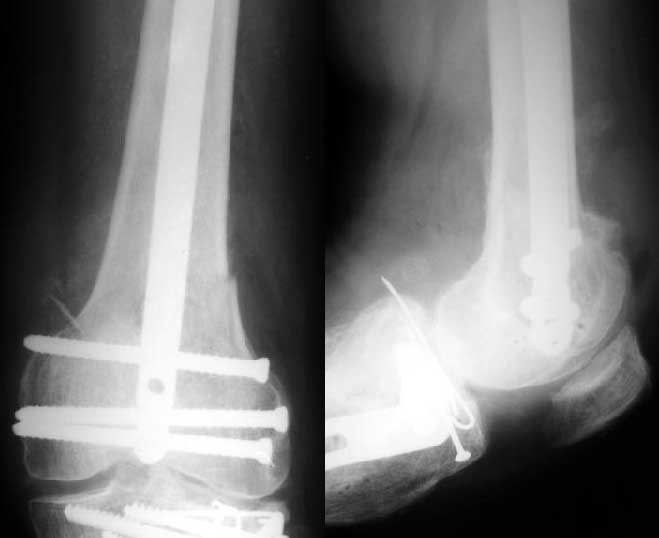

Sorry but I've just prepared postop images - attached. A solid 13 mm nail was used. A few degrees of recurvation appears to be which i missed on image intensifier. I'm still uncertain about

advantages/disadvantages of ante/retrograde nailing for such fractures.

the postop radiographs look excellent.

What do people think about driving an antegrade nail this distal as compared to retrograde nailing?

The antegrade nail in the case shown is probably into the knee joint slightly.

This case looks great but there must be some risk of splitting the condyles or other knee joint injury when driving an antegrade nail this distal. The antegrade nail also has entry site problems including variable injury to the hip muscles, heterotopic ossification, femoral neck fracture, and positioning difficulties. Overall the entry site problems seem about the same for the two techniques. If that is the case then the decision might come down to which one offers better distal fixation and that might be retrograde nail. If there are more entry site problems with retrograde nail than antegrade the antegrade nailing might be preferable even if the distal fixation isn't quite as good or reliable.

So, to me, it is a trade-off between benefits and risks for specific fracture patterns. In this case of a very distal femur shaft fracture the antegrade nail driven very distal in the femur looks extremely good. Without a comparative series we are left to base decisions on general principles, theory and related experience.